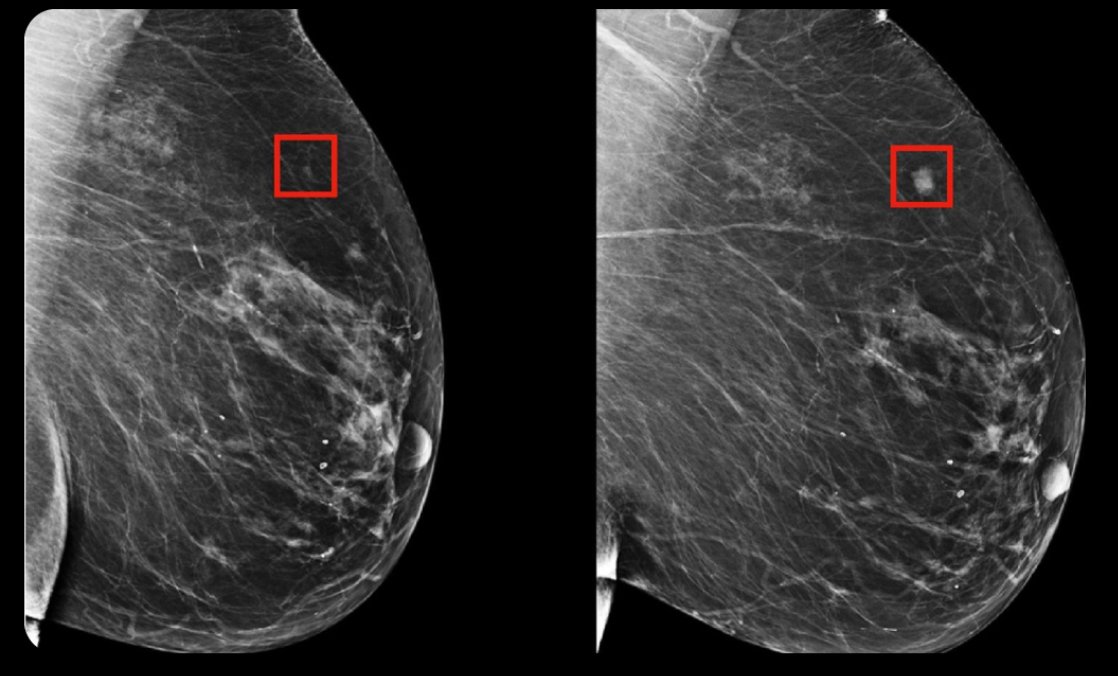

3. AI detects breast cancer 4 years before it develops.

Hungarian physicians are using an AI model that can detect breast cancer 4 years before it develops.